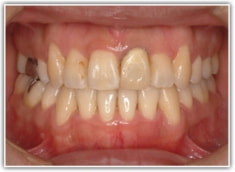

治療前

治療後(2年3ヶ月後)